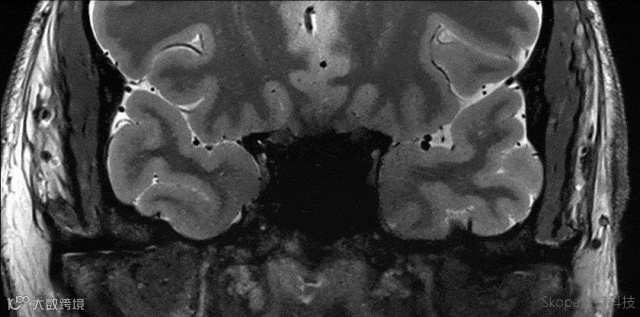

Sagittal T2 TSE

pTx有效改善了小脑区域图像均匀性。